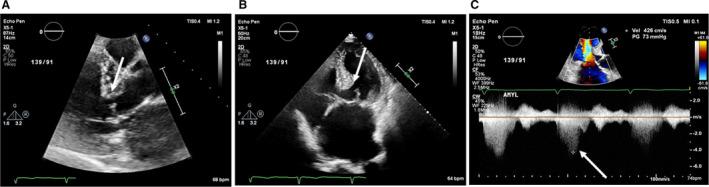

Background We report characteristics and outcomes of elderly patients with hypertrophic cardiomyopathy (HCM) with basal septal hypertrophy and dynamic left ventricular outflow tract obstruction. Methods and Results We studied 1110 consecutive elderly patients with HCM (excluding moderate or greater aortic stenosis or subaortic membrane, age 80±5 years [range, 75-92 years], 66% women), evaluated at our center between June 2002 and December 2018. Clinical and echocardiographic data, including maximal left ventricular outflow tract gradient, were recorded. The primary outcome was death and appropriate internal defibrillator discharge. Hypertension was observed in 72%, with a Society of Thoracic Surgeons (STS) score (8.6±6); while 80% had no HCM-related sudden cardiac death risk factors. Left ventricular mass index, basal septal thickness, and maximal left ventricular outflow tract gradient were 127±43 g/m, 1.7±0.4 cm, and 49±31 mm Hg, respectively. A total of 597 (54%) had a left ventricular outflow tract gradient >30 mm Hg, of which 195 (33%) underwent septal reduction therapy (SRT; 79% myectomy and 21% alcohol ablation). At 5.1±4 years, 556 (50%) had composite events (273 [53%] in nonobstructive, 220 [55%] in obstructive without SRT, and 63 [32%] in obstructive subgroup with SRT). One- and 5-year survival, respectively were 93% and 63% in nonobstructive, 90% and 63% in obstructive subgroup without SRT, and 94% and 84% in the obstructive subgroup with SRT. Following SRT, there were 5 (2.5%) in-hospital deaths (versus an expected Society of Thoracic Surgeons mortality of 9.2%). Conclusions Elderly patients with HCM have a high prevalence of traditional cardiovascular rather than HCM risk factors. Longer-term outcomes of the obstructive SRT subgroup were similar to a normal age-sex matched US population.

方法和结果 我们研究了 1110 例连续的老年 HCM 患者(不包括中度或重度主动脉瓣狭窄或主动脉瓣下膜,年龄 80±5 岁[范围 75-92 岁],66%为女性),这些患者于 2002 年 6 月至 2018 年 12 月在我们中心接受评估。记录了临床和超声心动图数据,包括最大左心室流出道梯度。主要终点为死亡和适当的内置除颤器放电。72%的患者有高血压,胸外科医师学会(STS)评分(8.6±6);而 80%的患者没有与 HCM 相关的心脏性猝死危险因素。左心室质量指数、基底室间隔厚度和最大左心室流出道梯度分别为 127±43 g/m、1.7±0.4 cm 和 49±31 mm Hg。共有 597 例(54%)左心室流出道梯度>30 mm Hg,其中 195 例(33%)接受室间隔减少治疗(SRT;79%心肌切除术和 21%酒精消融术)。在 5.1±4 年时,556 例(50%)发生复合事件(非梗阻性 273 例[53%],无 SRT 的梗阻性 220 例[55%],SRT 的梗阻性亚组 63 例[32%])。非梗阻性组的 1 年和 5 年生存率分别为 93%和 63%,无 SRT 的梗阻性亚组分别为 90%和 63%,SRT 的梗阻性亚组分别为 94%和 84%。SRT 后,有 5 例(2.5%)院内死亡(预期胸外科医师学会死亡率为 9.2%)。